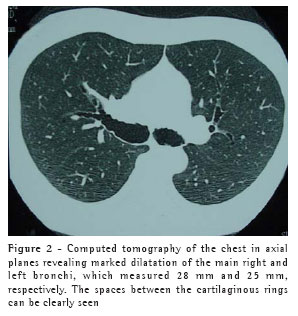

This treatment continued for four weeks, by which time the symptoms had been completely resolved. At that point, the patient was submitted to a computed tomography scan of the chest, which revealed that the areas of consolidation, although smaller in size, persisted in both lower lobes, and confirmed the abnormal widening of the trachea and main bronchi (Figures 1, 2 and 3). In the lower lobes, there was bilateral cylindrical bronchiectasis, which is consistent with a diagnosis of congenital tracheobronchomegaly, or Mounier-Kuhn syndrome. Pulmonary function tests revealed an increase in total lung capacity (123% of predicted) and residual volume (160% of predicted), with no other alterations. Currently, the patient remains asymptomatic, and has daily respiratory therapy sessions. Annual immunization against influenza has been recommended.

Congenital tracheobronchomegaly, or Mounier-Kuhn syndrome, is a rare clinical entity, described for the first time in 1932,(1) and characterized by marked tracheobronchial dilation and lower respiratory tract infections. It is predominantly found in male individuals in their 40s or 50s. Although the etiology of Mounier-Kuhn syndrome remains unknown, it is believed that it is related to a lack of smooth muscle and elastic connective tissue in the trachea and main bronchi, leading to herniation and even to the formation of diverticula between the cartilaginous rings. A finding of bronchiectasis, such as in the case in question, is uncommon.(2-3)

Diagnosis can usually be made by measuring the tracheal diameter, using only data from chest X-rays, in which the trachea can seen in profile and thus the diameter determined. Computed tomography of the chest, however, makes this measurement more precise. The limits are 3 cm for the transverse diameter of the trachea, and 2.4 cm and 2.3 cm for the transverse diameters of the main right and left bronchi, respectively.